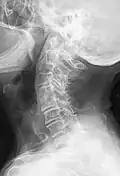

Als Blockwirbel wird die teilweise oder ganze Verschmelzung (Fusion) zweier oder mehrerer Wirbelkörper bezeichnet. Die Verschmelzung kann durch eine Entwicklungsstörung bedingt (dysontogenetischer Blockwirbel) oder im Laufe des Lebens erworben sein.

Eine dysontogenetische Blockwirbelbildung findet sich zum Beispiel beim Klippel-Feil-Syndrom.

Erworbene Blockwirbel können sich z. B. nach Entzündungen der Wirbel und Bandscheiben (z. B. nach Tuberkulose), nach Trauma oder bei ausgeprägter Degeneration der Bandscheiben und angrenzenden Wirbel (Osteochondrosis intervertebralis) ausbilden.